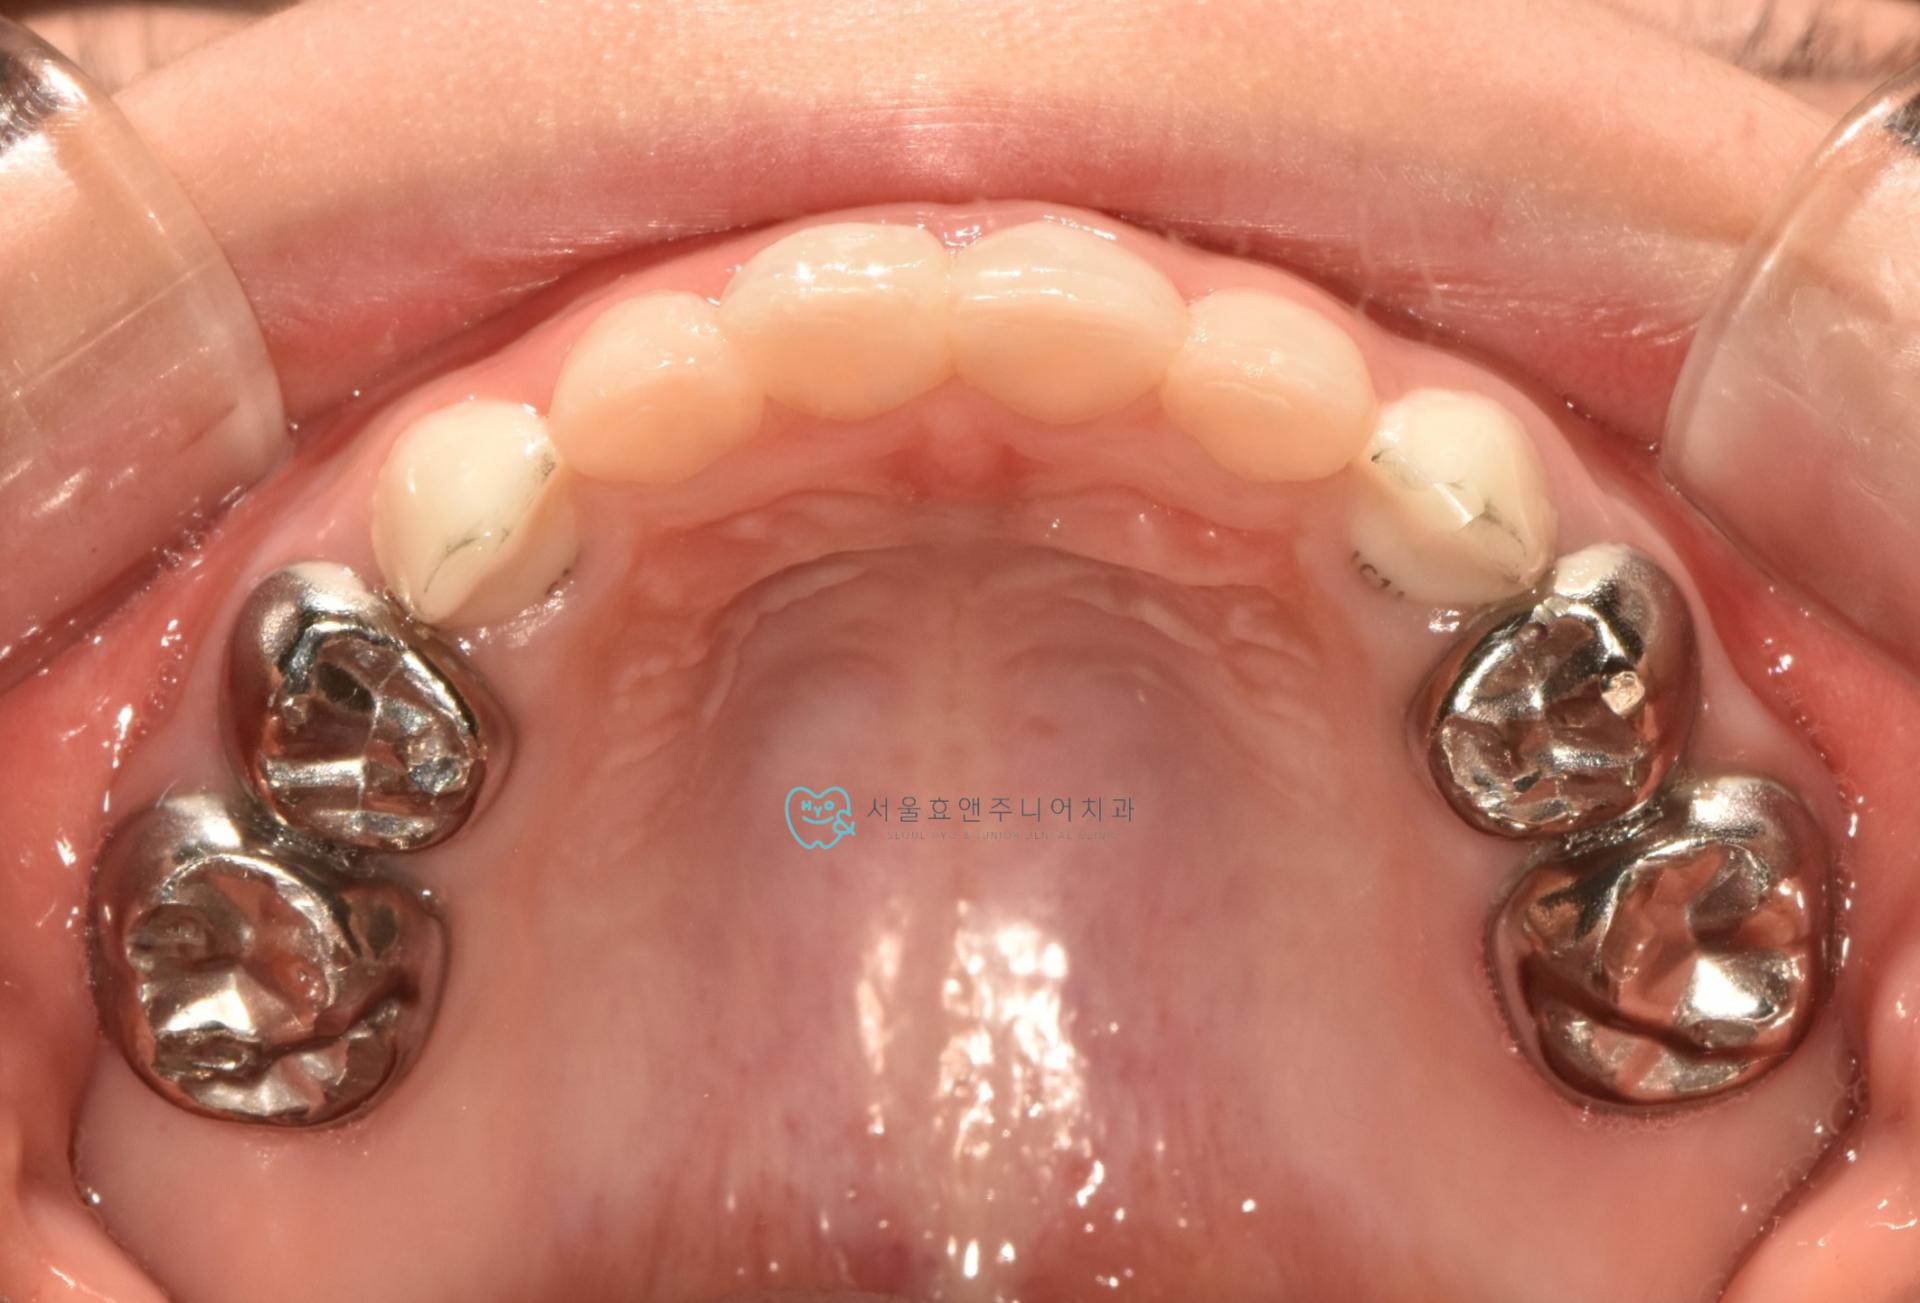

충치를 레진으로 치료한 뒤입니다. 치아의 양 벽면을 레진으로 깨끗하게 수복하였습니다.

수면치료 하에 앞니 4개를 모두 레진치료하였습니다. 충치의 범위가 넓어 레진치료하기가 까다로웠지만, 결과는 예쁘게 되었네요. 치아가 깨끗하고 예뻐져서 부모님도 아이도 만족하는 치료였으며 저도 보람을 느꼈습니다. 아직 첫번째 앞니는 2년정도 , 두번째 앞니는 3년 넘게 더 쓸것으로 보입니다.